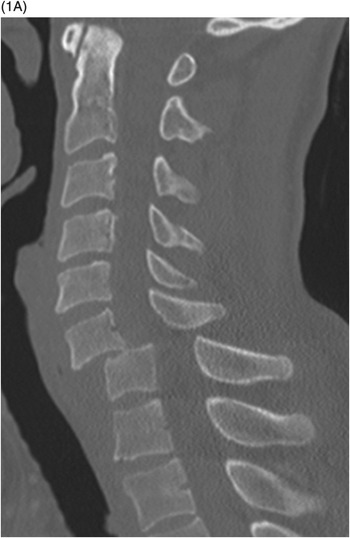

collapse of body from osteoporosis, kyphosis, trauma, or pathologic disease. Anterior wedge collapses, changing the shape to a wedge, best demoed on a lateral spine

jefferson fx

fx of anterior and posterior arches of C1 caused by severe axial loading (fall on head), best demoed by open mouth views

teardrop fx

comminuted vertebral body w/ triangular fragments extending from body; caused by compression & hyperflexion of c-spine, best demoed on lateral or CT